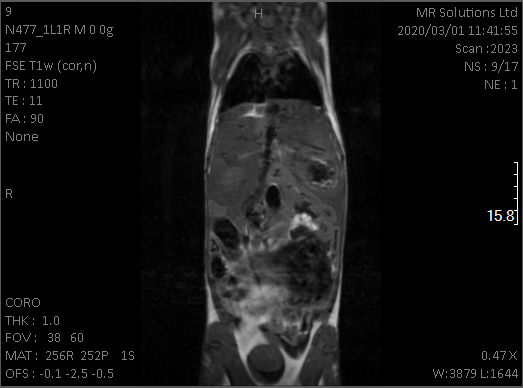

mri_liver

Mouse liver tumor